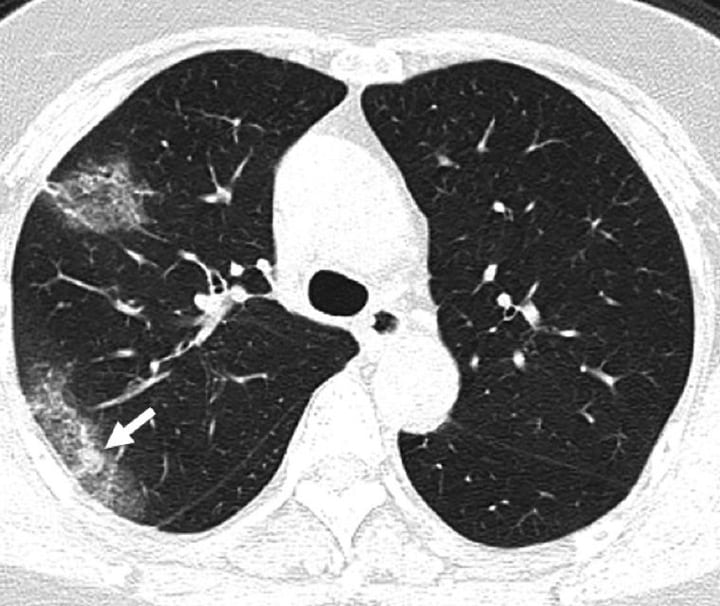

در موارد شدید مشابه پنومونی در ریهها مایع جمع میشود. این مایعات در سی تی اسکن ریه کرونایی به صورت لکههای سفید که کدورت شیشه مات نامیده میشود، توسط پزشک قابل تشخیص است.نقش تستهای آزمایشگاهی در تشخیص کرونا نسبت به سی تی اسکن ریه کرونایی پررنگتر است، اما برای یافتن شواهدی که پزشک به دنبالش هست مفید می باشد.تاثیر کرونا روی ریه بسیار شدید است و اسکن ریه کرونا گرفته با ریه سالم متمایز است. ریه طبیعی و سالم از کرونا در سی تی اسکن باید سیاه به نظر برسد.

ریه طبیعی و سالم از کرونا در سی تی اسکن باید سیاه به نظر برسد.معمولاً وجود تودههای کوچک بافت یا ندولهای ریوی که به صورت نقاط سفید ریز مشاهده میشوند، طبیعی است.اما سی تی اسکن ریه کرونایی لکههای سفید رنگی دارد که رادیولوژیستها از آن به عنوان «کدورت شیشه مات» یاد میکنند. در پایین تصویر کرونا در تست سلامت ریه از طریق سی تی اسکن ریه کرونایی را مشاهده کیکنید.

اسکن بیماران کرونا لکههای سفید رنگی دارد که رادیولوژیستها از آن به عنوان «کدورت شیشه مات» یاد میکنند.این علامت نشانگر عفونت شدید COVID-19 و ناشی از تجمع مایع در ریهها است. اما این علامت به تنهایی برای شناسایی ویروس کرونا مفید نیست. «این علامت در سایر عفونتها نیز قابل مشاهده است. عفونتهای باکتریایی، ویروسی یا حتی گاهی غیر عفونی و حتی در استعمال سیگار الکترونیک.»اما در مورد علائم ریه کرونا گرفته، لکه های قابل توجهی در سی تی اسکن ریه کرونایی هستند که تا لبههای ریههای بیمار امتداد مییابند. این چیزی نیست که خیلی شایع باشد. ما این مورد را در سندرم تنفسی حاد (SARS) و سندرم تنفسی خاورمیانه (MERS) مشاهده کردهایم.SARS و MERS هر دو از خانواده کرونا ویروس هستند.ریه و کرونا با هم مرتبط هستند و برای تست سلامتی ریه باید مطمئن شوید که دچار کرونا نشدهاید و یا اگر مبتلا شدید، کرونا را به سرعت مداوا کنید. شما از طریق درمانکده میتوانید تست کرونا در خانه یا محل خود بدهید و جواب را در ۲ روز کاری دریافت کنید:تجزیه و تحلیل نزدیک به ۱۴۰ اسکن ویروس کرونا نشان میدهد که «کدورت شیشه مات» در هر دو ریه از مشخصههای سی تی اسکن ریه کرونایی است.A: سی تی اسکن در روز پنجم ظهور علائمB: سی تی اسکن در روز نوزدهم ظهور علائم